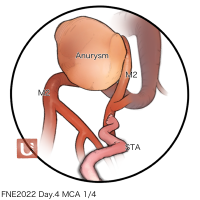

FEN2022シリーズ